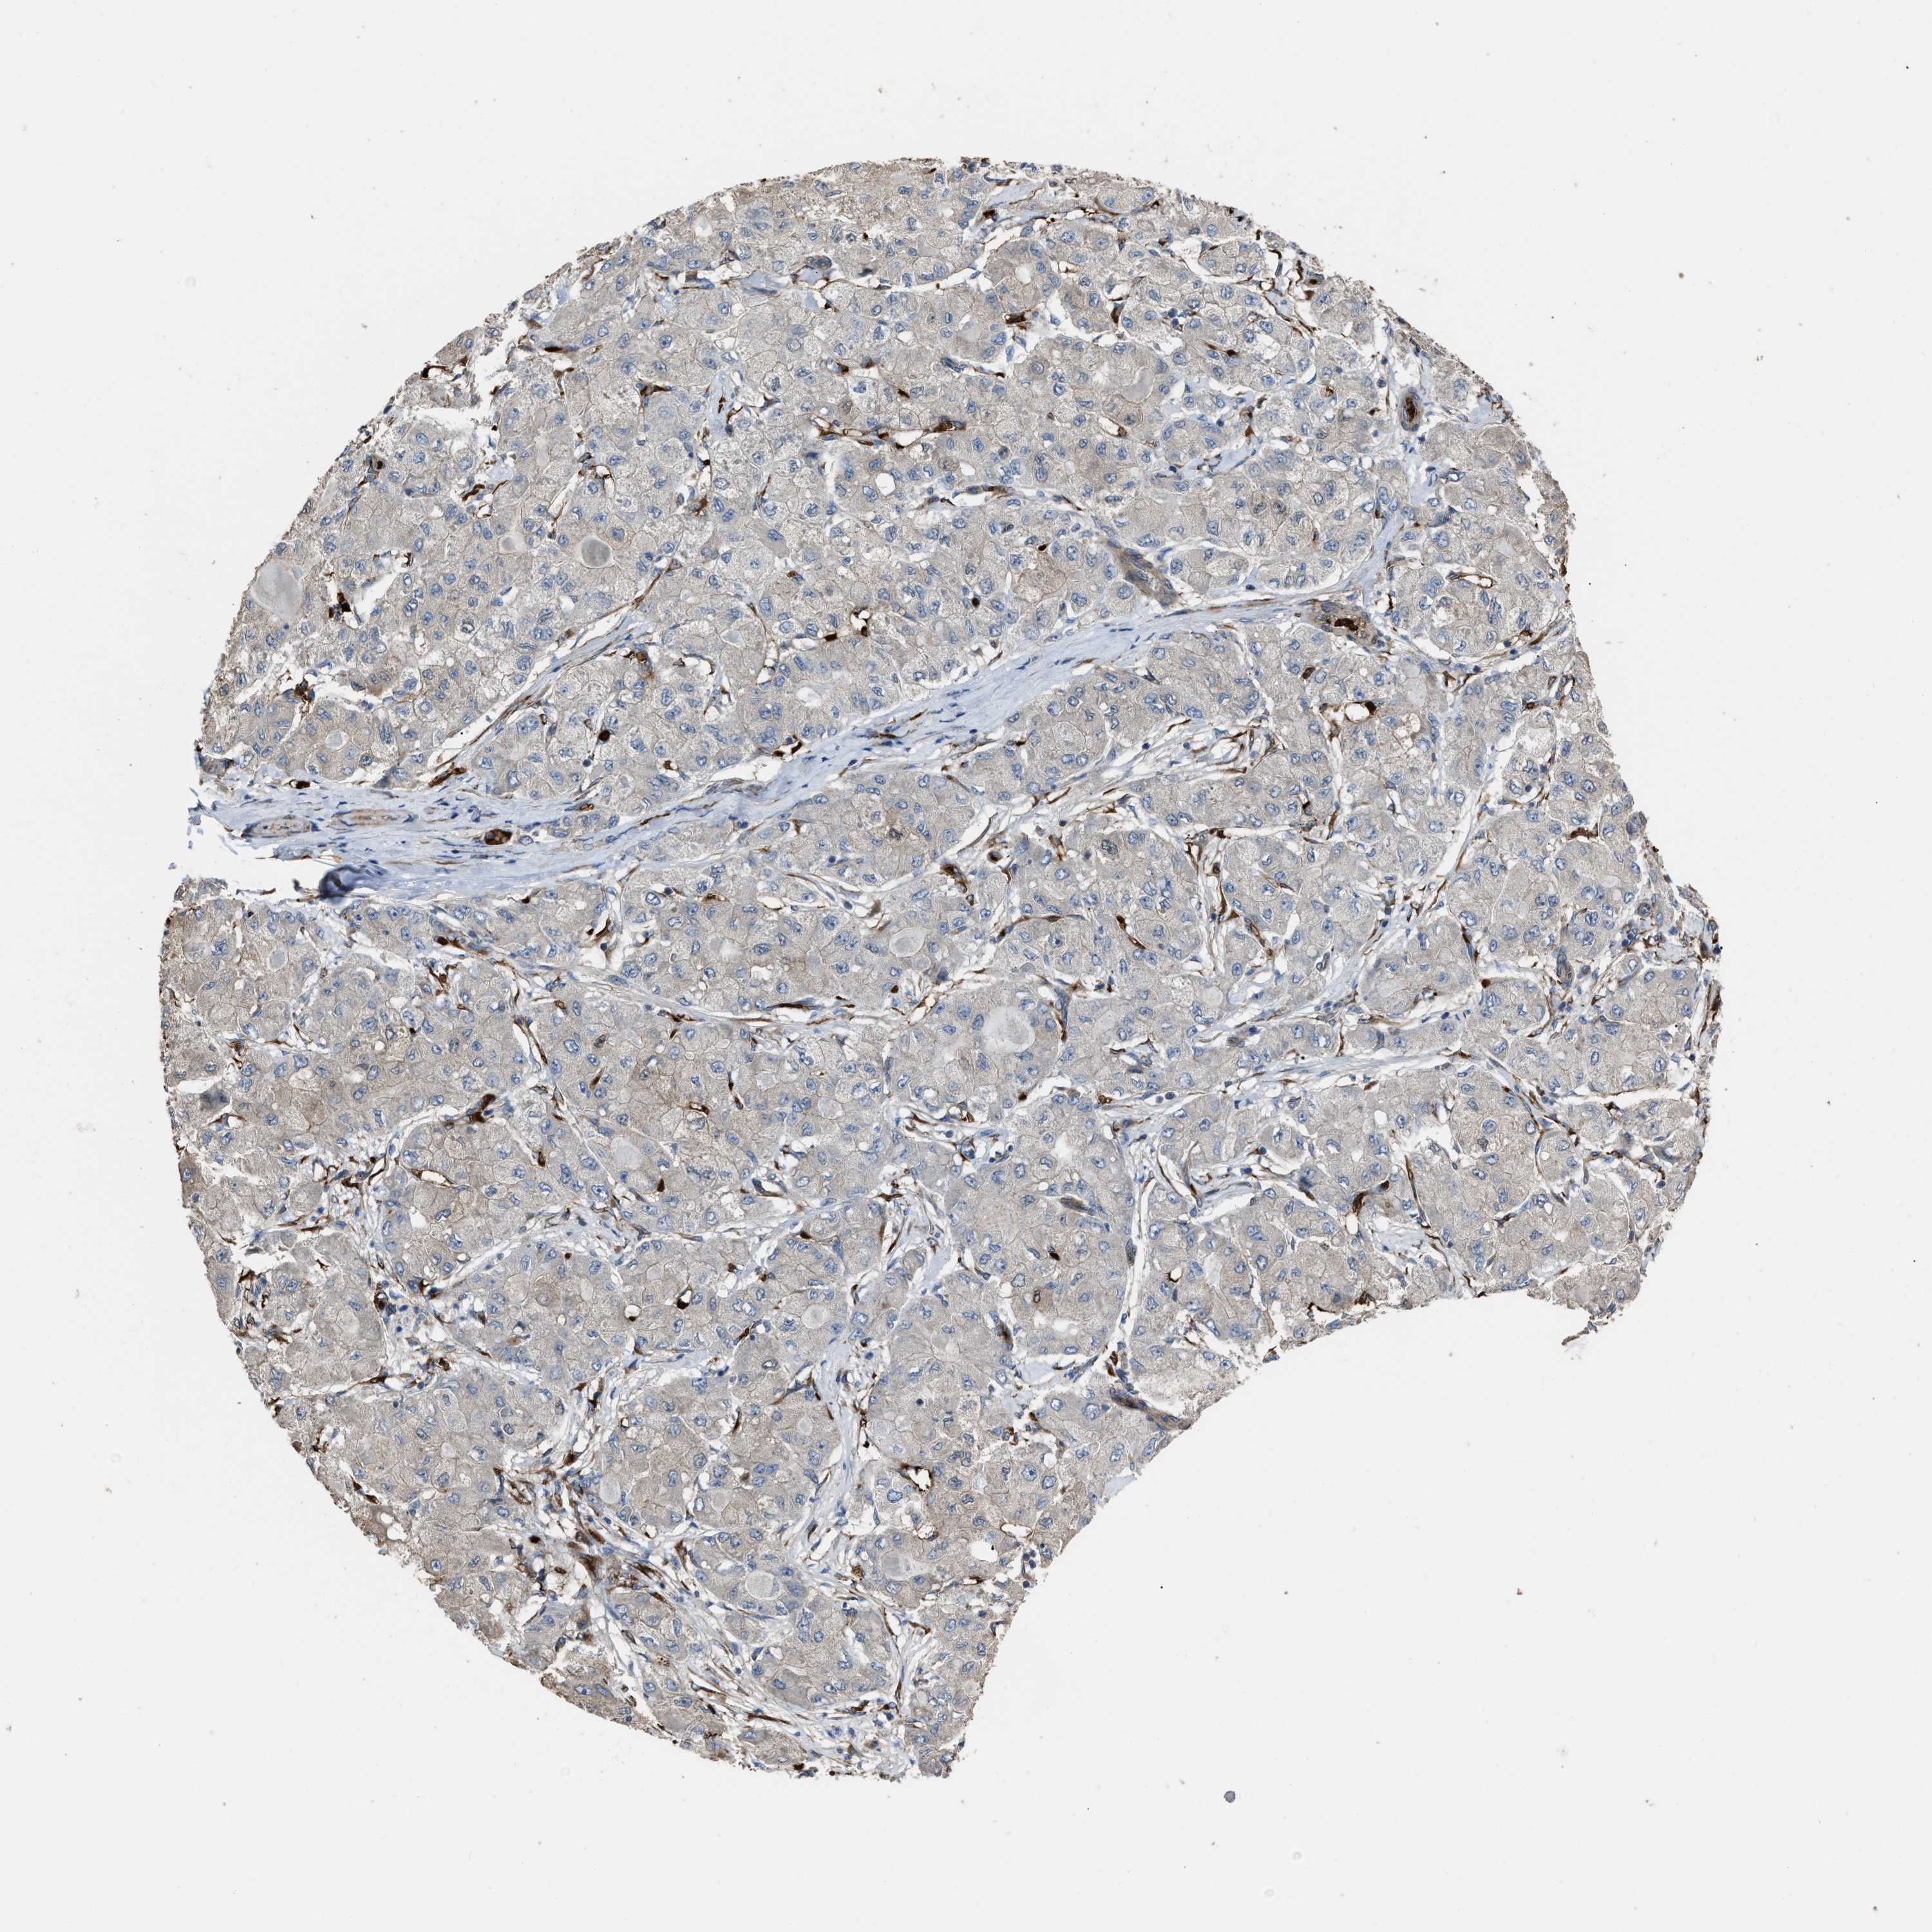

LIVER CANCER - Protein expressioni

A mouse-over function shows sample information and annotation data. Click on an image to view it in a full screen mode. Samples can be filtered based on level of antibody staining by selecting one or several of the following categories: high, medium, low and not detected. The assay and annotation is described here.

Note that samples used for immunohistochemistry by the Human Protein Atlas do not correspond to samples in the TCGA dataset.

Antibody stainingi

Antibody staining in the annotated cell types in the current human tissue is reported as not detected, low, medium, or high, based on conventional immunohistochemistry profiling in selected tissues. This score is based on the combination of the staining intensity and fraction of stained cells.

Each image is clickable and will lead to virtual microscopy that enables deeper exploration of all samples and also displays staining intensity scores, fraction scores and subcellular localization as well as patient and tissue information for each sample.

Antibody HPA019601

Antibody CAB008667

Staining

High

Medium

Low

Not detected

Intensity

Strong

Moderate

Weak

Negative

Quantity

>75%

75%-25%

<25%

None

Location

Nuclear

Cytoplasmic/membranous

Cytoplasmic/membranous,nuclear

Carcinoma, Hepatocellular, NOS

Cholangiocarcinoma